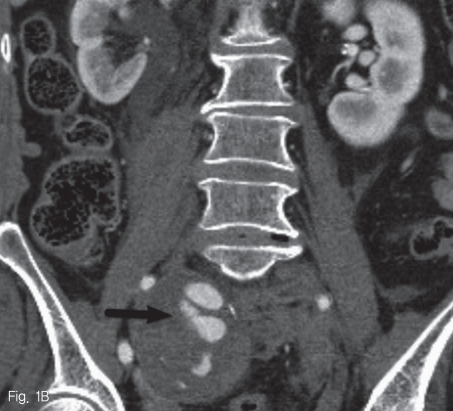

내원 당시 시행한 CT상 복부 대동맥 전체와 양측 총장골동맥 그리고 오른쪽 내장골동맥에 걸쳐 동맥류가 있으며 내부에 혈전이 동반되어 있었음. 오른쪽 내장골동맥의 직경은 최대 약 15mm로 측정되었으며 근위부에 거짓동맥류와 조영제의 혈관 외 유출이 확인됨. 또한 후복막강 혈종이 동반되었으며 이는 오른쪽 신장의 상극 주변까지 퍼져 있었음 (Fig. 1a and 1b).

Fig 1B

Coronal CT image

B. shows pseudoaneurysm(black arrow) and extravasation of contrast media.